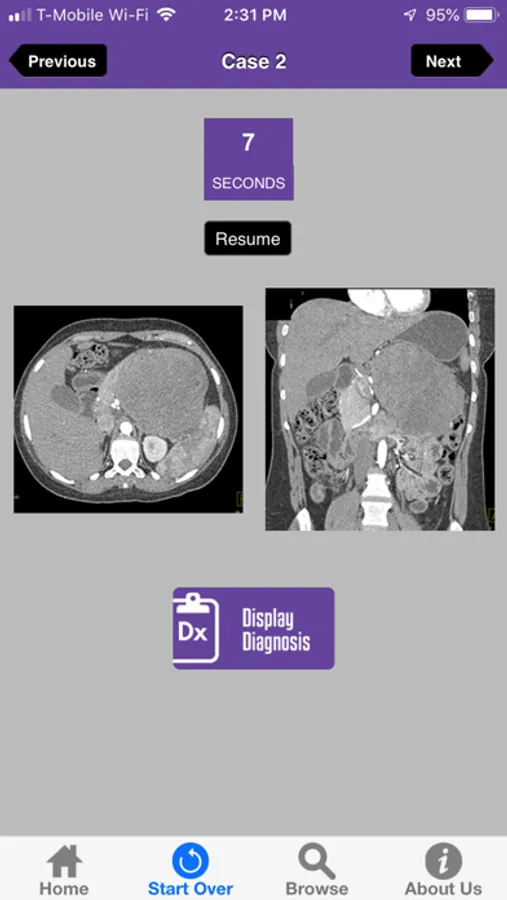

Test your pancreas imaging interpretation skills! This App includes CT images for 50 pancreatic tumor cases. You can review the cases at your own pace or play against the clock by taking the timed quiz to diagnose each case in under 10 seconds. After 10-seconds, the diagnosis will be displayed.

CTisus Challenge: The Pancreas Screenshots